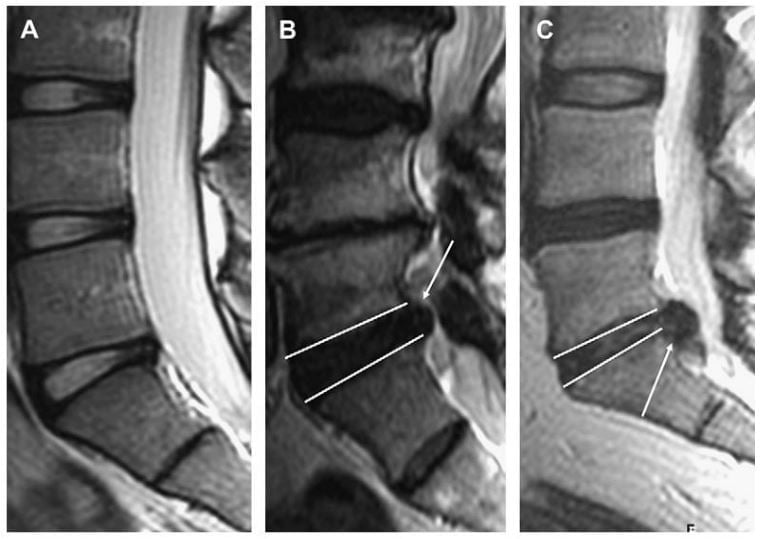

Thoát vị là protrusion nếu khoảng cách lớn nhất của các bờ chất bị lồi nhỏ hơn các bờ của chất đĩa đệm bình thường khi xác định trên cùng một mặt phẳng. Ví dụ, nếu khoảng cách trên dưới của các bờ chất đĩa đệm bị thoát vị nhỏ hơn hoặc bằng các bờ của chất đĩa đệm bình thường trên cùng một mặt phẳng (khi đo ở mặt cắt sagittal hoặc coronalđể đánh giá độ lan trên dưới), thì nó được phân loại là protrusion (Hình 3). Đo chiều trên dưới gần như luôn tốt nhất ở mặt phẳng sagittal. Lồi khu trú khi xác định trên mặt phẳng axial là phần thoát vị liên quan với ít hơn một nửa đĩa đệm (< 180 độ chu vi đĩa đệm). Protrusion có thể được phân loại thêm thành khu trú hoặc đáy rộng dựa vào mức độ đĩa đệm bị tổn thương. Protrusion khu trú liên quan với ít hơn 25% (hoặc 90 độ ) của chu vi đĩa đệm,trong khi protrusion đáy rộng nằm giữa 25% đến 50% (90-180 độ) của chu vi đĩa đệm (Hình 4).

Hình 3. Hình sagittal T2W mô tả protrusion đĩa đệm L5-S1 (mũi tên trắng). Ghi nhận chất đĩa đệm thoát vị không vượt qua giới hạn của bờ trên và bờ dưới đĩa đệm (tức là vượt qua chỗ nối đĩa đệm/bề mặt thân sống). Khi xác định trên mặt cắt sagittal, thoát vị đĩa đệm này là protrusion.

Hình 4. Axial T2W qua đĩa đệm L4-5 cho thấy protrusion đĩa đệm. Protrusion khu trú (A) và đáy rộng (B) được vẽ bởi đường gạch chấm trắng. Protrusion khu trú liên quan ít hơn 25% (hoặc 90 độ) của chu vi đĩa đệm, trong khi protrusion đáy rộng nằm trong khoảng 25% đến 50% (90-180 độ) của chu vi đĩa đệm.

Ngược với protrusion, thoát vị đĩa đệm là extrusion nếu khoảng cách lớn nhất giữa các bờ của chất bị thoát vị lớn hơn các bờ của đáy thoát vị khi đo trên cùng một mặt phẳng. Ví dụ, nếu chất bị thoát vị vượt qua giới hạn của bờ trên hoặc bờ dưới đĩa đệm hay bề mặt thân sống thấy trên mặt phẳng sagittal thì đây là extrusion đĩa đệm (Hình 5). Nếu chất đĩa đệm bị extrusion có cổ hẹp và phần thoát vị rộng hơn khi thấy trên mặt phẳng axial thì đó cũng là một minh hoạ rõa nhất cho extrusion (Hình 6). Ngược lại, protrusion thì không thì vuợt qua bờ trên và bờ dưới đĩa đệm trên hình sagittal và có thể có cổ đáy rộng với phần protrusion của đĩa đệm không rộng như cổ của protrusion (xem Hình 5, Hình 6).

Hình 5. Hình MRI sagittal cột sống thắt lưng cho thấy đĩa đệm bình thường (A), protrusion L5-S1 (B), extrusion kèm di lệch xuống dưới ngang mức L5-S1 (mũi tên) (C). Các đường trắng chỉ ra bờ trên và bờ dưới đĩa đệm L5-S1 ở hình B và C. Protrusion không vượt qua chiều trên – dưới đĩa đệm trên hình sagittal (B), trong khi extrusion vượt qua bờ này (C).